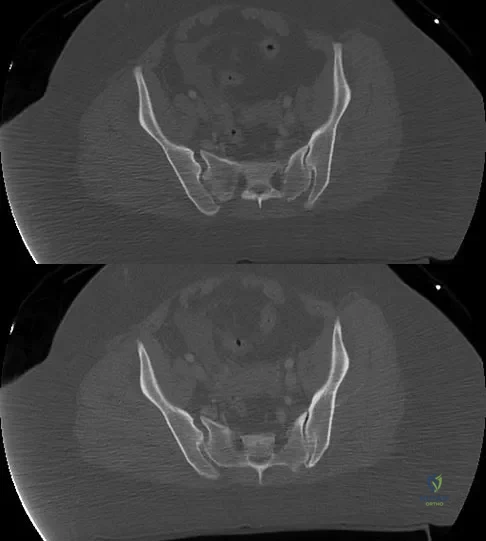

To avoid an injury to the L5 nerve root when placing an S1 sacroiliac screw, what area of the sacrum should be avoided on the lateral C arm image shown in Figure 21?